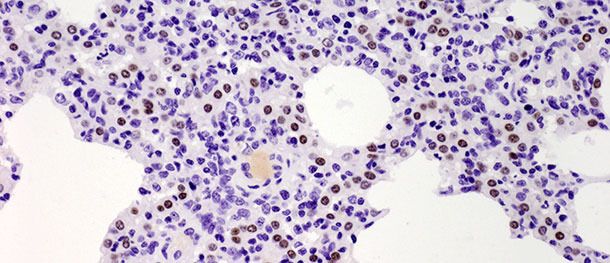

Les pneumocytes de type II sont des cellules de forme cubique qui sont souvent localisées à l’insertion des septums alvéolaires. Dans le tissu pulmonaire des mammifères, ils constituent 60% de toutes les cellules alvéolaires épithéliales, mais ils couvrent seulement environ 5% de la superficie alvéolaire. Leur rôle le plus important est la synthèse, la sécrétion et le recyclage du surfactant pulmonaire qui diminue la tension superficielle alvéolaire, prévenant le collapsus pendant l’expiration. L’autre fonction importante des pneumocytes de type II se trouve dans leur potentialité proliférative. Quand les pneumocytes de type I sont endommagés, ceux du type II agissent comme des cellules souches pour les remplacer et, avec le temps, se différencient en pneumocytes de type I. Dans le challenge décrit ci-dessus, le nombre de ces cellules a augmenté significativement sur les 10 jours PI (photo 3) et n’a pas diminué à 21 jours PI. Bien que l’étude se soit terminée à 10 jours PI et que l’on n’a pas observé de guérison histologique totale (restitutio ad integrum) dans le groupe infecté, les animaux ont récupéré de la maladie clinique et le nombre élevé de pneumocytes de type II après l’inoculation autant sur les phases initiales que sur les phases finales de la maladie ont démontré leur importance dans la guérison du tissu pulmonaire (description en détails dans Balka et al.2013. J Comp Pathol).

Photo 3 : les points marron indiquent le noyau des pneumocytes de type II identifiés avec des anticorps anti-TTF-1. On a observé une augmentation significative du nombre de cellules positives à 10 jours après l’infection avec un isolat de type I sous-type 1. IHC 200x.